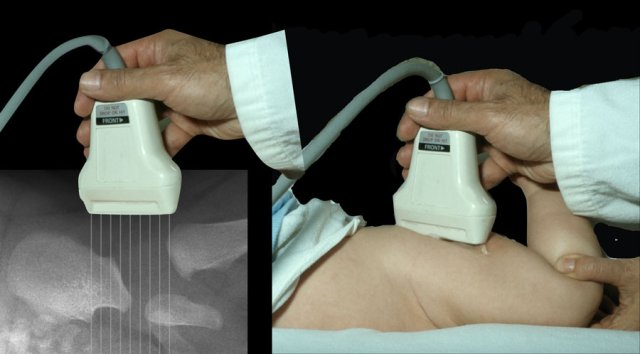

With ultrasound we are looking at the same anatomic structures as on the x-ray.

The ultrasound images are in the coronal plane (figure).

Because the infant is lying on its side the anatomy is displayed in a horizontal fashion instead of vertical (figure)

And this is the way the ultrasound image is displayed on the screen of the ultrasound machine

A lineair, high frequency probe is used.

The focus is set at the acetabular edge.

It is important to display an image in the coronal plane at the level of the triradiate cartilage, which is the synchondrosis between the iliac, ischial and pubic bones which form the acetabulum.